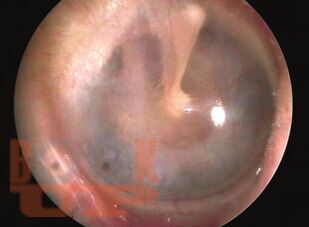

Textbook of Ear Nose and Throat Diseases

Otorhinolaryngology has been one of the widely-studied subjects and the range of patients under this speciality is very high. With a genuine intention to equip the reader with all the revised, comprehensive details of all disorders pertaining to this speciality, this edition proves to be the most exhaustive and embracive. This book is one of the most-read of all the available literature on ENT problems for the past 30 years. The compendious approach to impregnate the minds of the readers with the basic concepts of ENT, it is a must-have resource for the undergraduates, aspiring ENT specialists, and the practitioners. This fully-revised new edition of the book provides the reader with the updated details of the recent advances in the field of ENT disorders. Organized by anatomical region, each section provides the relevant anatomy and physiology, comprehensive covering of the related disorders, their investigations and diagnosis, and the proper management of the cases in the most detailed and easy-to-understand language. A few new chapters on management of neck masses, chemotherapy in head or neck tumors, otologic concerns in a syndromic child, and histopathology of common ENT diseases have also been included. Many new highly-instructive illustrations have been included to enhance the comprehensiveness of the text. Meticulous description of the all the disorders which leave an indelible imprint in the mind of the reader. MCQs have been included at the end of each section to aid the students in self-assessment, and to prepare for various, examinations.